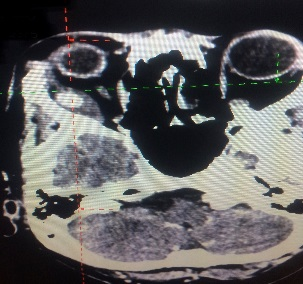

Any tumour mass can occur within the bony socket of the eye. It may occur as a primary tumour or secondary tumour (metastatic disease). It is also essential to know the difference between a benign and malignant tumour. After discussing the symptoms and signs, a detailed clinical examination and some clinical tests, Dr Nazila will order for an imaging such as CT scan or MRI and advise for surgery.

Thyroid eye disease can be as a result of high, normal or low thyroid hormone levels of patients affected with thyroid disease. Depending on the severity of thyroid eye disease, management will be tailored accordingly. Most patients will only require medical treatment but a small proportion will require surgical intervention to correct the appearance and functionality of the eye. In acute cases where medical treatment is refractory, surgical orbital decompression is the only way to salvage a patient's vision. At other times, when thyroid disease has achieved stability, the bulging eye appearance can be alleviated by orbital decompression. Squint from thyroid eye disease can be addressed surgically and eyelid surgery can be performed.